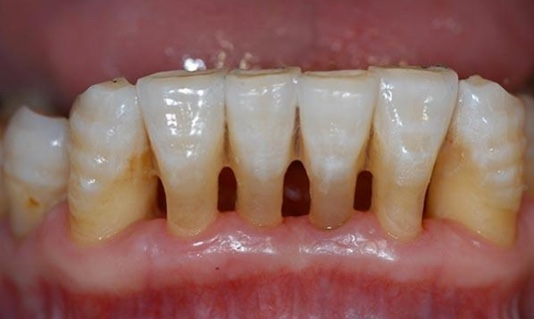

那么牙结石的危害有哪些呢?1、口臭。百分之八十的口腔异味都是源于口腔,牙周病是主要原因之一,减少菌斑是消除口臭的主要方法2、牙龈萎缩。牙石的长期堆积会压迫牙龈,使牙龈红肿、萎缩,牙缝变大,更进一步加重食物嵌塞。更易导致邻面龋的发生。3、牙松动。牙龈炎进一步加重发展成牙周炎,牙槽骨吸收,牙根暴露,牙齿越来越松,最终脱落。所谓“老掉牙”就是由牙石引起的。

4、牙根敏感。牙根暴露于外界当中,冷热酸甜刺激更为敏感,影响进食,吃啥啥不香。